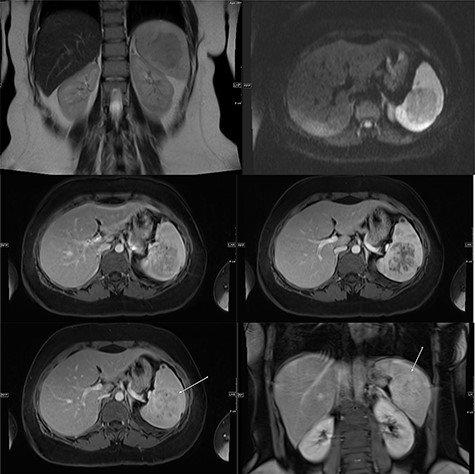

Abdominal ultrasonography showed a 5.0 × 5.0 cm well-defined, rounded, lobulated and hypoechoic vascular solid splenic lesion with no increased transmission or calcification. This lesion had vessels radiating from the center to the periphery (Fig. 1). Further evaluation with contrast-enhanced computed tomography (CT) of the abdomen showed a 6.0 × 5.6 × 4.4 cm solitary, rounded and lobulated non-calcified mass in the spleen, demonstrating heterogeneous, linear and nodular arterial enhancement with progressive filling in the portal venous and delayed phases (Fig. 2).

Ultrasound images with Doppler showing a well-defined rounded hypoechoic mass with vascularity in the peripheral areas as well as inside the lesion with no through transmission.

(Top) coronal T2 WI MR Image showing a hypointense lesion in the spleen, which is not showing any diffusion restriction (right image); (middle images) post-contrast axial T1 WI MR image showing hypointense lesion with patchy contrast enhancement in the center (middle right image); the lesion becomes further isointense on delayed image (middle left image); (bottom) MRI of abdomen T1 weighted axial (bottom left) and coronal (bottom right) post-contrast images showing a lesion in the spleen (arrow) with peripheral and septal enhancement with a hypoenhancing center.